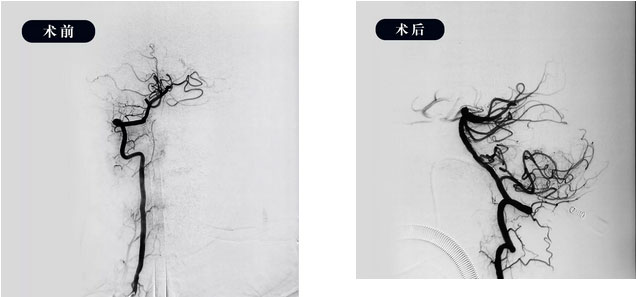

▲ 取栓前后DSA造影圖

10:15,在征得家屬同意后,患者被送入手術(shù)室,全麻下行全腦血管造影示:右側(cè)椎動(dòng)脈為優(yōu)勢(shì)血供動(dòng)脈,基底動(dòng)脈起始部閉塞,遠(yuǎn)端血流受限,必須及時(shí)取栓干預(yù)。

取栓支架到達(dá)血栓處后,開(kāi)始多次抽吸、支架拉栓,歷時(shí)兩個(gè)多小時(shí),取出大量血栓,基底動(dòng)脈正向血流恢復(fù),雙側(cè)大腦后動(dòng)脈顯影良好,達(dá)到TICI-III級(jí),完全灌注。復(fù)查術(shù)后正側(cè)位造影血流正常,即刻床旁CT顯示顱內(nèi)未見(jiàn)出血。